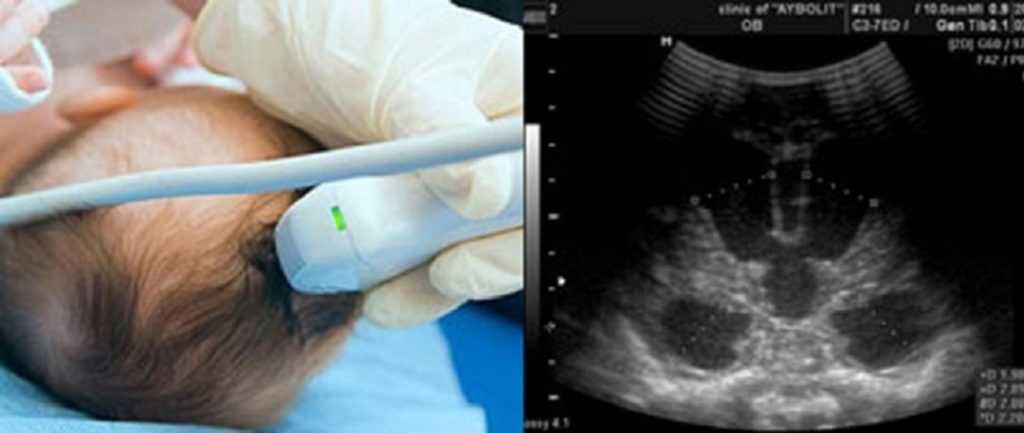

Кому показана НСГ?

Это основной метод выявления структурной патологии головного мозга у новорождённых. Основным показанием для проведения диагностики является отклонение неврологического статуса младенца вкупе с нарушением ряда лабораторных показателей.

Метод бесценный, если состояние ребёнка тяжёлое и не возможна его транспортировка в отделение функциональной диагностики для проведения МРТ.

Нейрохирургические операции несут за собой высокий риск, так как сложна ориентация в полости черепа и структурах мозга.

Ультрасонография может помочь хирургу обеспечить максимально быстрое и точное попадание хирургического инструмента в цель, используя минимум технических средств.

УЗИ помогает определить локализацию, глубину залегания, размеры хирургической мишени, выбрать оптимальный доступ при минимальном операционном окне.

Требуется ли специальная подготовка к исследованию?

До внедрения данного метода малышей приходилось подвергать действию общего наркоза, если возникали подозрения на нарушения в работе ЦНС. Обследование головного мозга новорожденных при помощи НСГ является совершенно безопасной процедурой. Для малыша оно не представляет никакого вреда. Процесс проведения УЗИ не сопровождается неприятными ощущениями, не доставляет дискомфорта и не причиняет боли ребенку.

Никакой специальной предварительной подготовки к процедуре не предусмотрено. Допускается присутствие мамы во время НСГ, врач ответит на все ее вопросы, если в ходе исследования ее что-то заинтересует.

Процедура осуществляется при наличии большого родничка. Возможно проведение УЗИ в состоянии сна или бодрствования младенца. Врач сможет сделать все необходимые манипуляции, даже если малыш ведет себя беспокойно или плачет — на результаты это никак не повлияет.